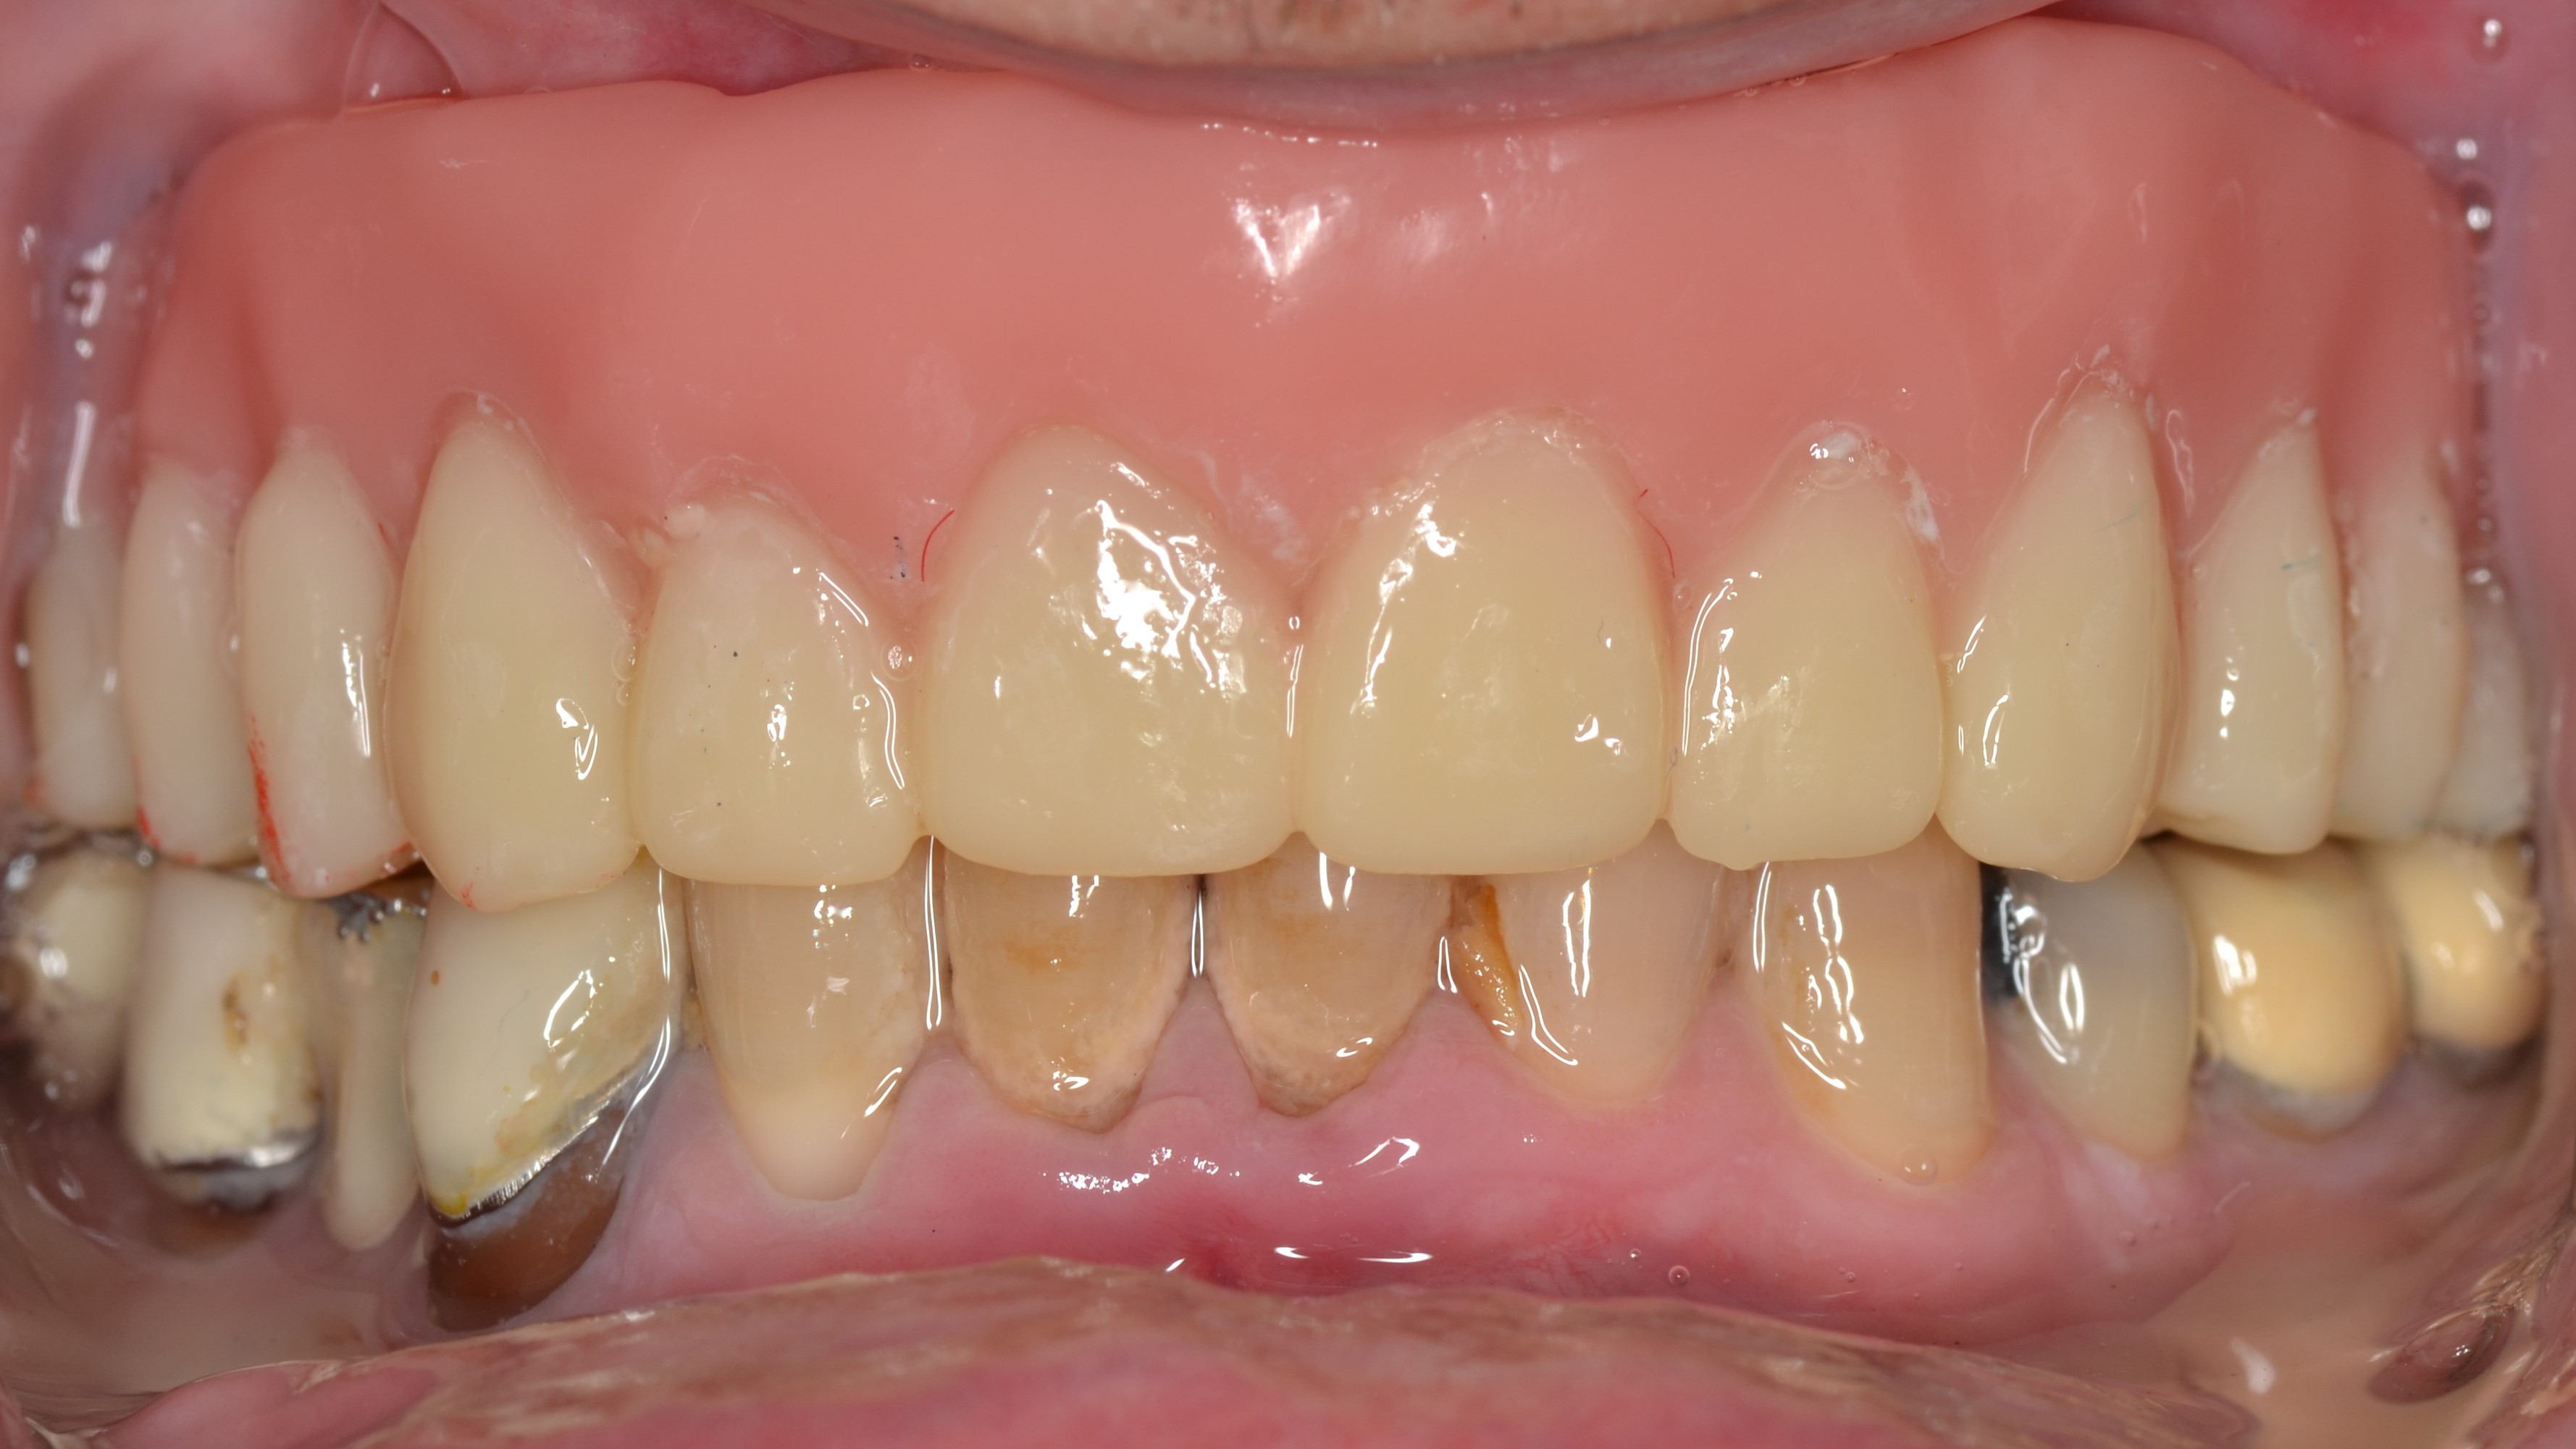

We extracted the remaining upper teeth and made him a full acrylic denture.

He was extremely happy with the improvement in his aesthetics and function.